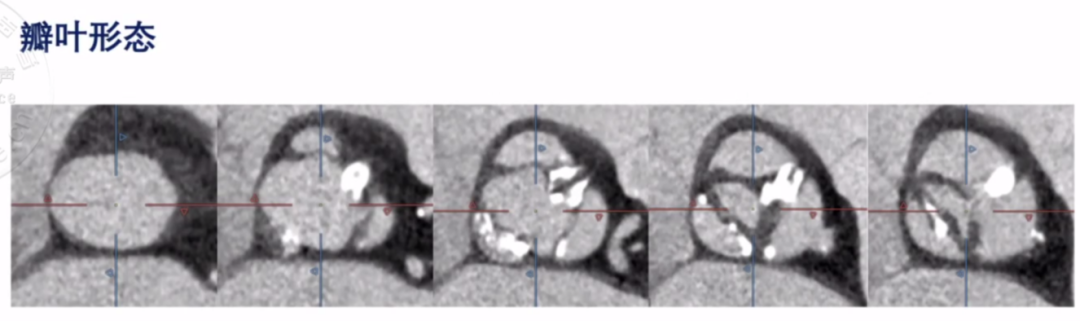

在中国主动脉瓣狭窄患者群体中, 二叶式主动脉瓣畸形的比例高于西方国家, 对于该类患者,释放时瓣膜下滑导致瓣中瓣为一个比较常见的问题。杜润教授通过一例超大瓣环功能性二叶瓣患者的讲解,演示如何通过瓣膜选择及电动可回收释放技巧降低瓣膜下滑的风险。

该患者为76岁男性,NYHA III级,STS评分8.2%。术前CT分析显示,功能性二叶瓣,左右冠瓣融合合并钙化。

图片

左右冠瓣有非常严重的钙化脊-为功能性二叶瓣

瓣环符合#30瓣膜,左室流出道呈梯形

综合患者病史及CT检测结果,在手术策略制定过程中,选择瓣膜尺寸时,因为该患者二叶瓣畸形合并严重钙化,左冠瓣及右冠瓣有非常严重的钙化脊,可能导致瓣膜扩张不充分及瓣膜释放时下滑的风险,最终选择“downsize”策略植入VitaFlow®27mm瓣膜并在稍高位置释放。